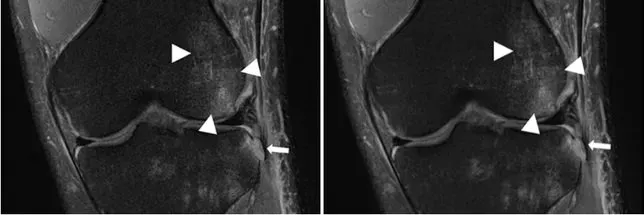

دو عکس پایین از یک زانوی آسیبدیده، گرفته شده است. با وجود داشتن یک تفاوت بزرگ، این دو عکس بسیار شبیه به یکدیگر هستند. تنها تفاوت موجود در این عکسها استفاده از MRI همراه با کمک هوش مصنوعی در عکس سمت چپی است که با سرعت بیشتری نسبت به عکس سمت راستی ثبت شده است.

عکس سمت چپ با استفاده از ادغام هوش مصنوعی با MRI گرفته شده است